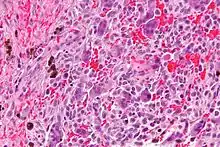

Micrograph of a central giant cell granuloma showing the characteristic giant cells with surrounding cells that have nuclei that are dissimilar to those in the giant cells. H&E stain.

Histology of CGCG shows a lobulated mass composed of vascular connective tissue and multinucleated giant cells (osteoclasts). The giant cells may be diffusely located throughout the lesion or focally aggregate in the lesion, often clustered around hemorrhagic areas hemosiderin deposits. Lobules of the lesion can be separated by fibrous tissue or even thin layer of bone or osteoid that can be seen radiographically. Giant cells are thought to form in response to signals produced by fibroblasts and blood vessels or as a response to cytokines.[2][5]